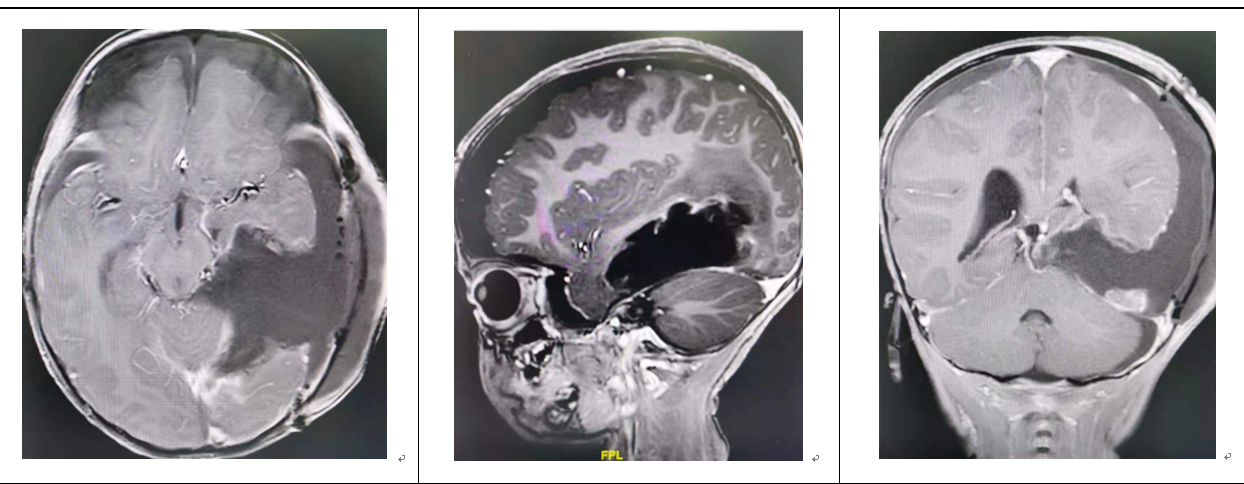

通过仔细检查,王翦初步判定小烨颅内巨大肿物位于左侧颞顶枕叶,考虑很可能是恶性室管膜瘤。

2岁的小烨头颅最长径15厘米,而肿瘤直径达11厘米,几乎波及整个左侧大脑。巨大的肿瘤破坏左侧颞顶枕叶脑组织,会影响患儿的语言、肢体活动、视觉和认知和记忆功能等神经功能障碍。更糟糕的是,肿瘤将大脑“掌管”呼吸和心跳的中枢——脑干往右侧推移2厘米,颅高压明显,孩子随时都可能有生命危险。

术前的小烨:小脑袋都被肿瘤撑大了

术前MR(上图):头的最大直径15厘米,而肿瘤直径达到了惊人的11厘米